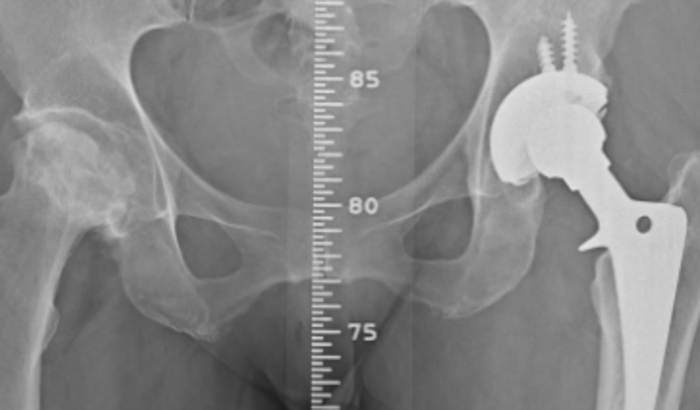

De prótese total de quadril direito.

Já uso uma prótese total de quadril esquerdo.